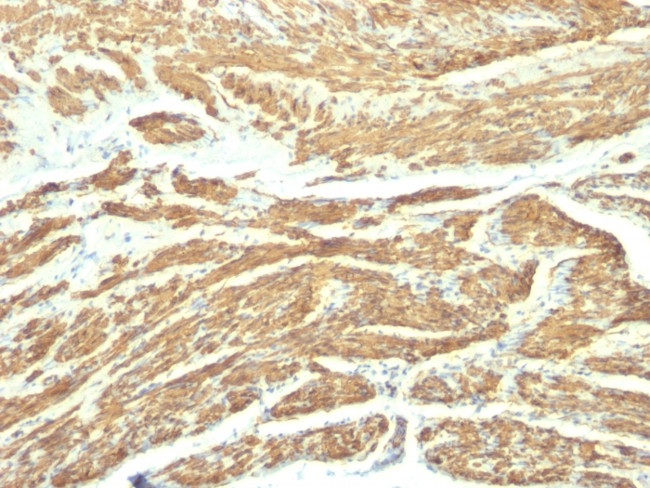

Caldesmon, HMW (h-Caldesmon) (Smooth Muscle Marker) Monoclonal Antibody (SPM168)

Caldesmon is a developmentally regulated protein involved in smooth muscle and non muscle contraction. Two closely related variants of human caldesmon have been identified which differ in their electrophorectic mobility and cellular distribution. The h caldesmon variant (120 - 150 kDa) is predominantly expressed in smooth muscle whereas l caldesmon (70 - 80 kDa) is found in non-muscle tissue and cells. Neither of the two variants has been detected in skeletal muscle.